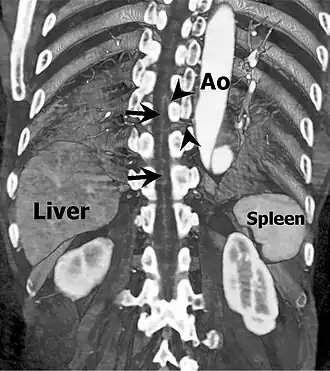

Артерия Адамкевича (также называемая артерия поясничного утолщения; большая передняя радикуломедуллярная артерия) — кровоснабжает нижнюю часть спинного мозга (начиная с позвонка от Т6 — T10). Анастомозирует с передней спинальной артерией спинного мозга.[1] Названа в честь польского врача и патологоанатома Альберта Войцеха Адамкевича.

Имеет диаметр от 0,8 до 2мм[1][3]. Может ответвляться от спинного ответвления дорсальной ветви одной из межрёберных артерий (обычно в пределах от 5--й до 11й), подрёберной артерии или одной из поясничных (чаще всего из первой левой)[4][1]. Поднимается по средней сагиттальной передней поверхности спинного мозга, обычно на расстояние меньше двух с половиной позвонков, при анастомозе с передней спинальной артерией принимает характерный «шпилечный поворот», в остальном имеет прямое течение по сравнению с более извилистой передней радикуломедуллярной веной.[3]